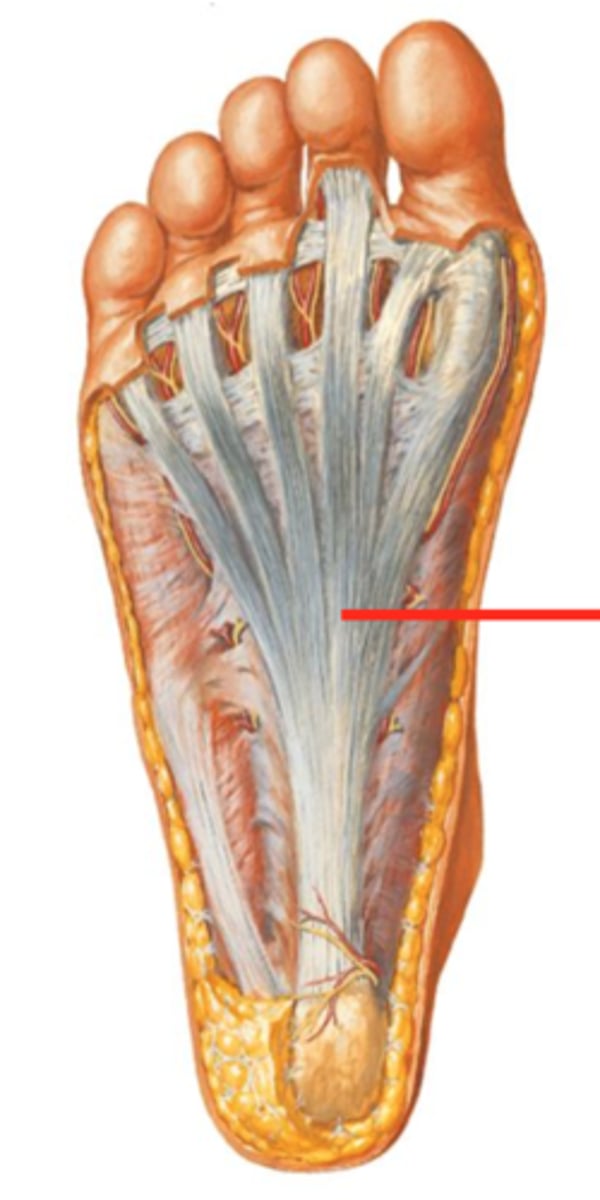

Plantar aponeurosis

Medial plantar nerve

nerve in pink

Lateral plantar nerve

nerve in pink